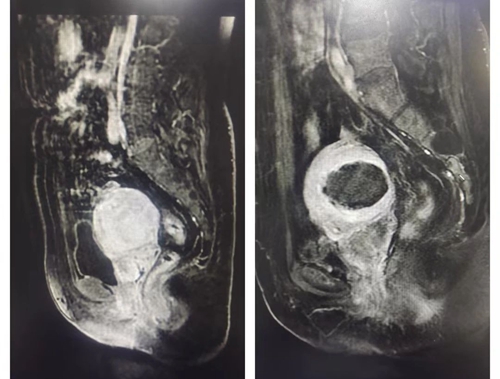

王女士被收治入院進(jìn)行系統(tǒng)治療,腫瘤標(biāo)志物以及盆腔核磁等檢查結(jié)果顯示王女士果然患有子宮腺肌病,而且合并了盆腔子宮內(nèi)膜異位癥!為滿足患者強(qiáng)烈保留子宮的愿望,治療團(tuán)隊(duì)決定通過(guò)微無(wú)創(chuàng)治療替代傳統(tǒng)切除子宮的治療方式幫王女士解決病痛。